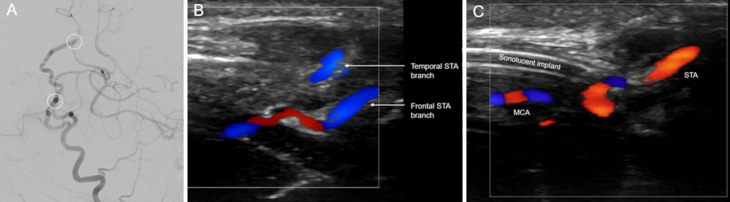

Observations: A 38-year-old male with OI type I presented with a symptomatic left internal carotid artery (ICA) occlusive dissection managed with endovascular revascularization and stenting. Follow-up surveillance imaging identified an incidental right ICA dissection, also treated with stenting. Four years later, the patient experienced new right hemispheric symptoms. He was found to have progressive right ICA dissection on best medical management. Following an unsuccessful restenting attempt, he underwent a successful double-barrel superficial temporal artery-to-middle cerebral artery (STA-MCA) bypass to restore cerebral perfusion with no perioperative complications. Six-month follow-up DSA confirmed a patent bypass with robust flow, and the patient remained asymptomatic 1 year postoperatively.